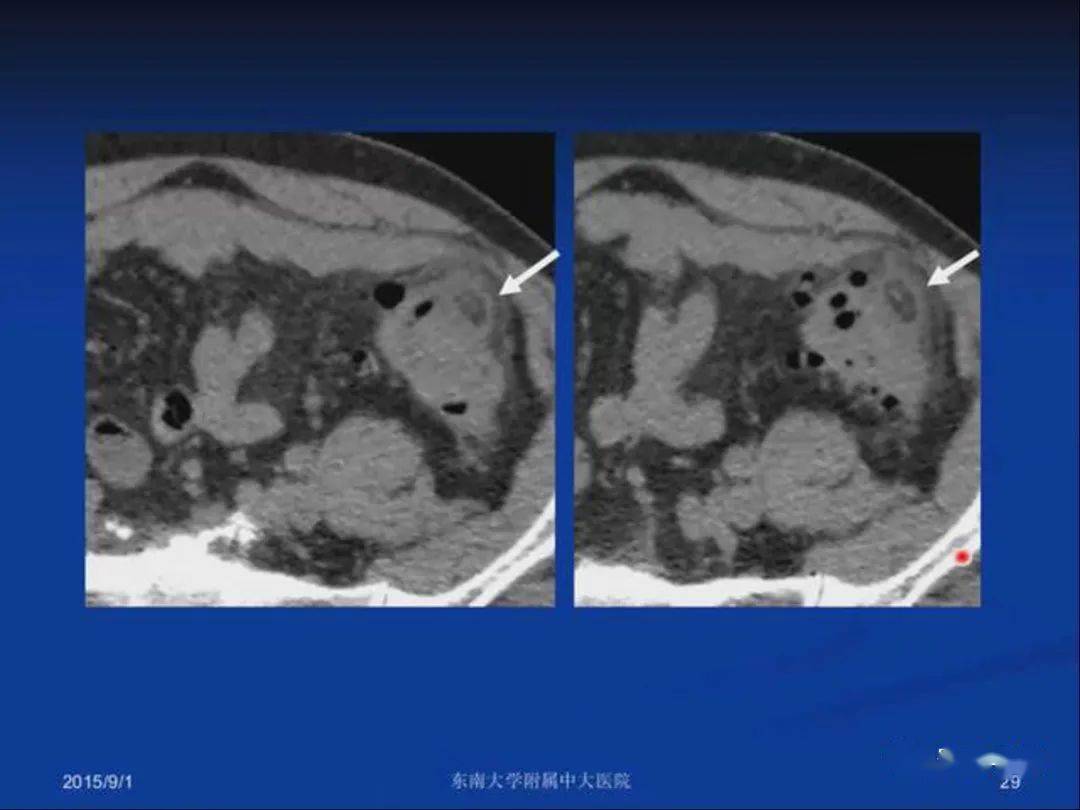

肠脂垂炎

急性原发性肠脂垂炎ct诊断与鉴别诊断